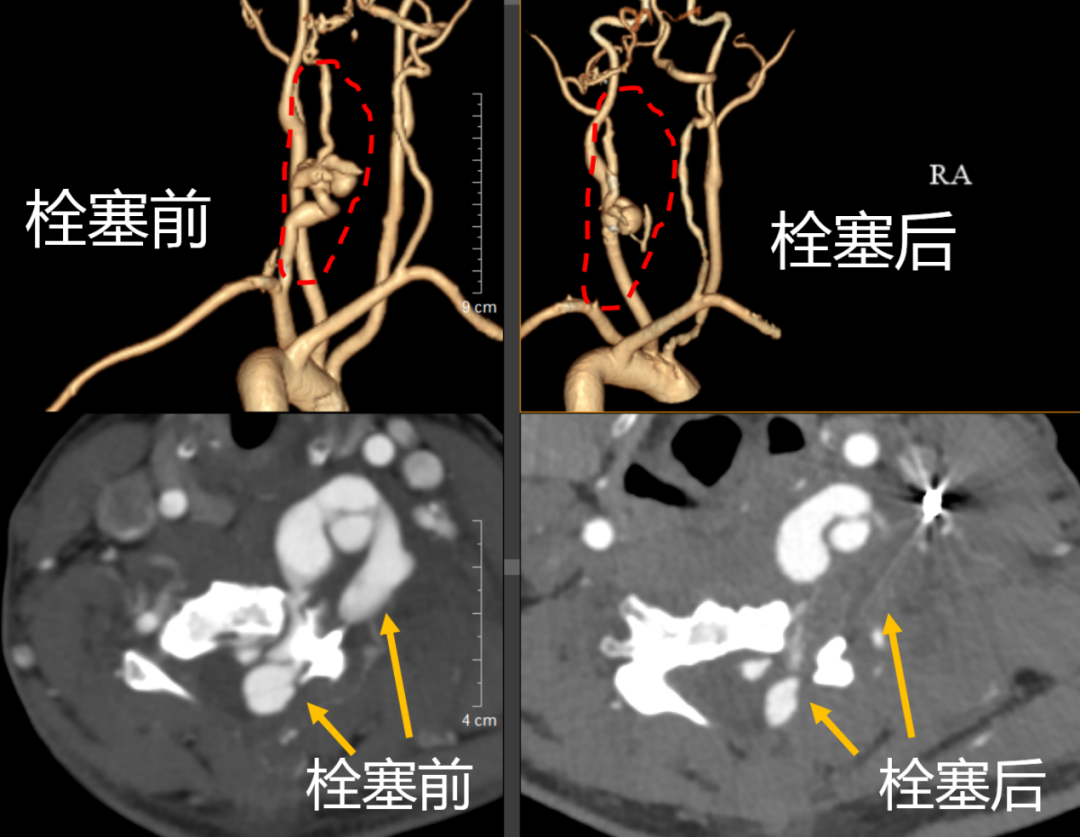

近几年,小娟的颈椎后凸畸形逐渐加重并出现了神经受压症(颈椎后凸角度约70°),入院检查颈胸段脊柱半脱位、脊髓受压,同时因颈椎长期畸形造成椎动脉继发病变,形成复杂的椎动脉-动静脉瘘。检查发现,其椎动脉V2段(第6颈椎水平)向前延伸至椎体前方,向后延伸至椎管,椎管内动脉比脊髓还粗大,且多条血管参与动静脉瘘供应,颈脊髓受压严重。

患者入院后,脊柱外科一科高度重视,组织了多学科协作(MDT)团队。由神经外科医生黄伟佳率先开展介入下椎动脉畸形栓塞术,成功栓塞了3条导致椎动脉畸形的关键血管,随后患者转回脊柱外科一科实施矫形手术。按照治疗计划,医生先为患者进行了为期两周的头环重力牵引,以改善畸形,评估脊髓和神经矫形的耐受程度,为手术创造有利条件。两周后,黄敏军与脊柱外科一科主任王亮合作,为患者制定详细手术方案,并择期进行单一颈后路矫形重建手术,手术过程十分顺利,历时约4小时,出血量不到 600毫升。手术有效保留了颈椎部分活动度,且颈椎后凸畸形矫形率达到 70%,由术前的70°减少至术后21°。